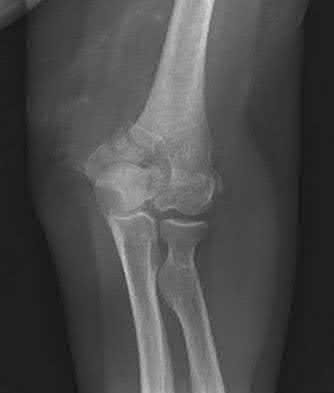

Figure A is an AP radiograph of a posterior knee dislocation. Figure B is a lateral showing the same injury.